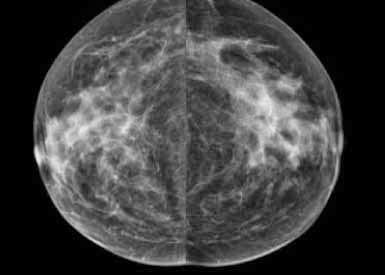

She finally came out and said I was free to go and apologized for the wait, but that my scans had looked so different from last year they really wanted to take a close look. That freaked me out for a moment and I asked her what she meant. Apparently my dense breast tissue wasn't so dense anymore. I asked if she minded showing me, and she took me in to look at the scans, from last year and this year, side by side. The 'suspicious" areas were diminished, and some completely gone. Apparently one of the perqs to aging (and having a hysterectomy) is that your hormones are no longer playing such great havoc. By next year they might look even less dense. So there was a "Yippee!!!" feeling, after all.